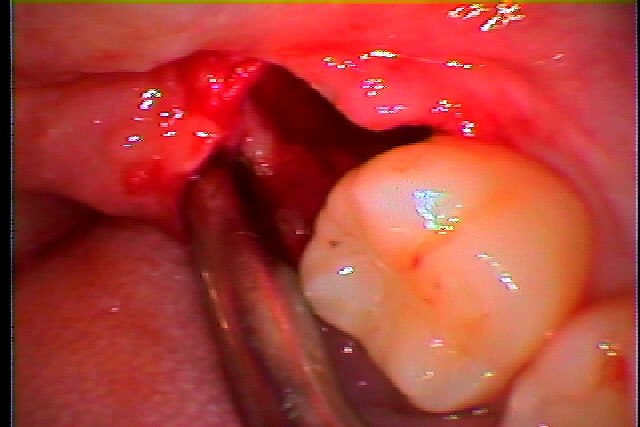

麻酔をかけ、歯肉を少し開いて歯を診ていきます

歯冠部を分割抜歯していきました